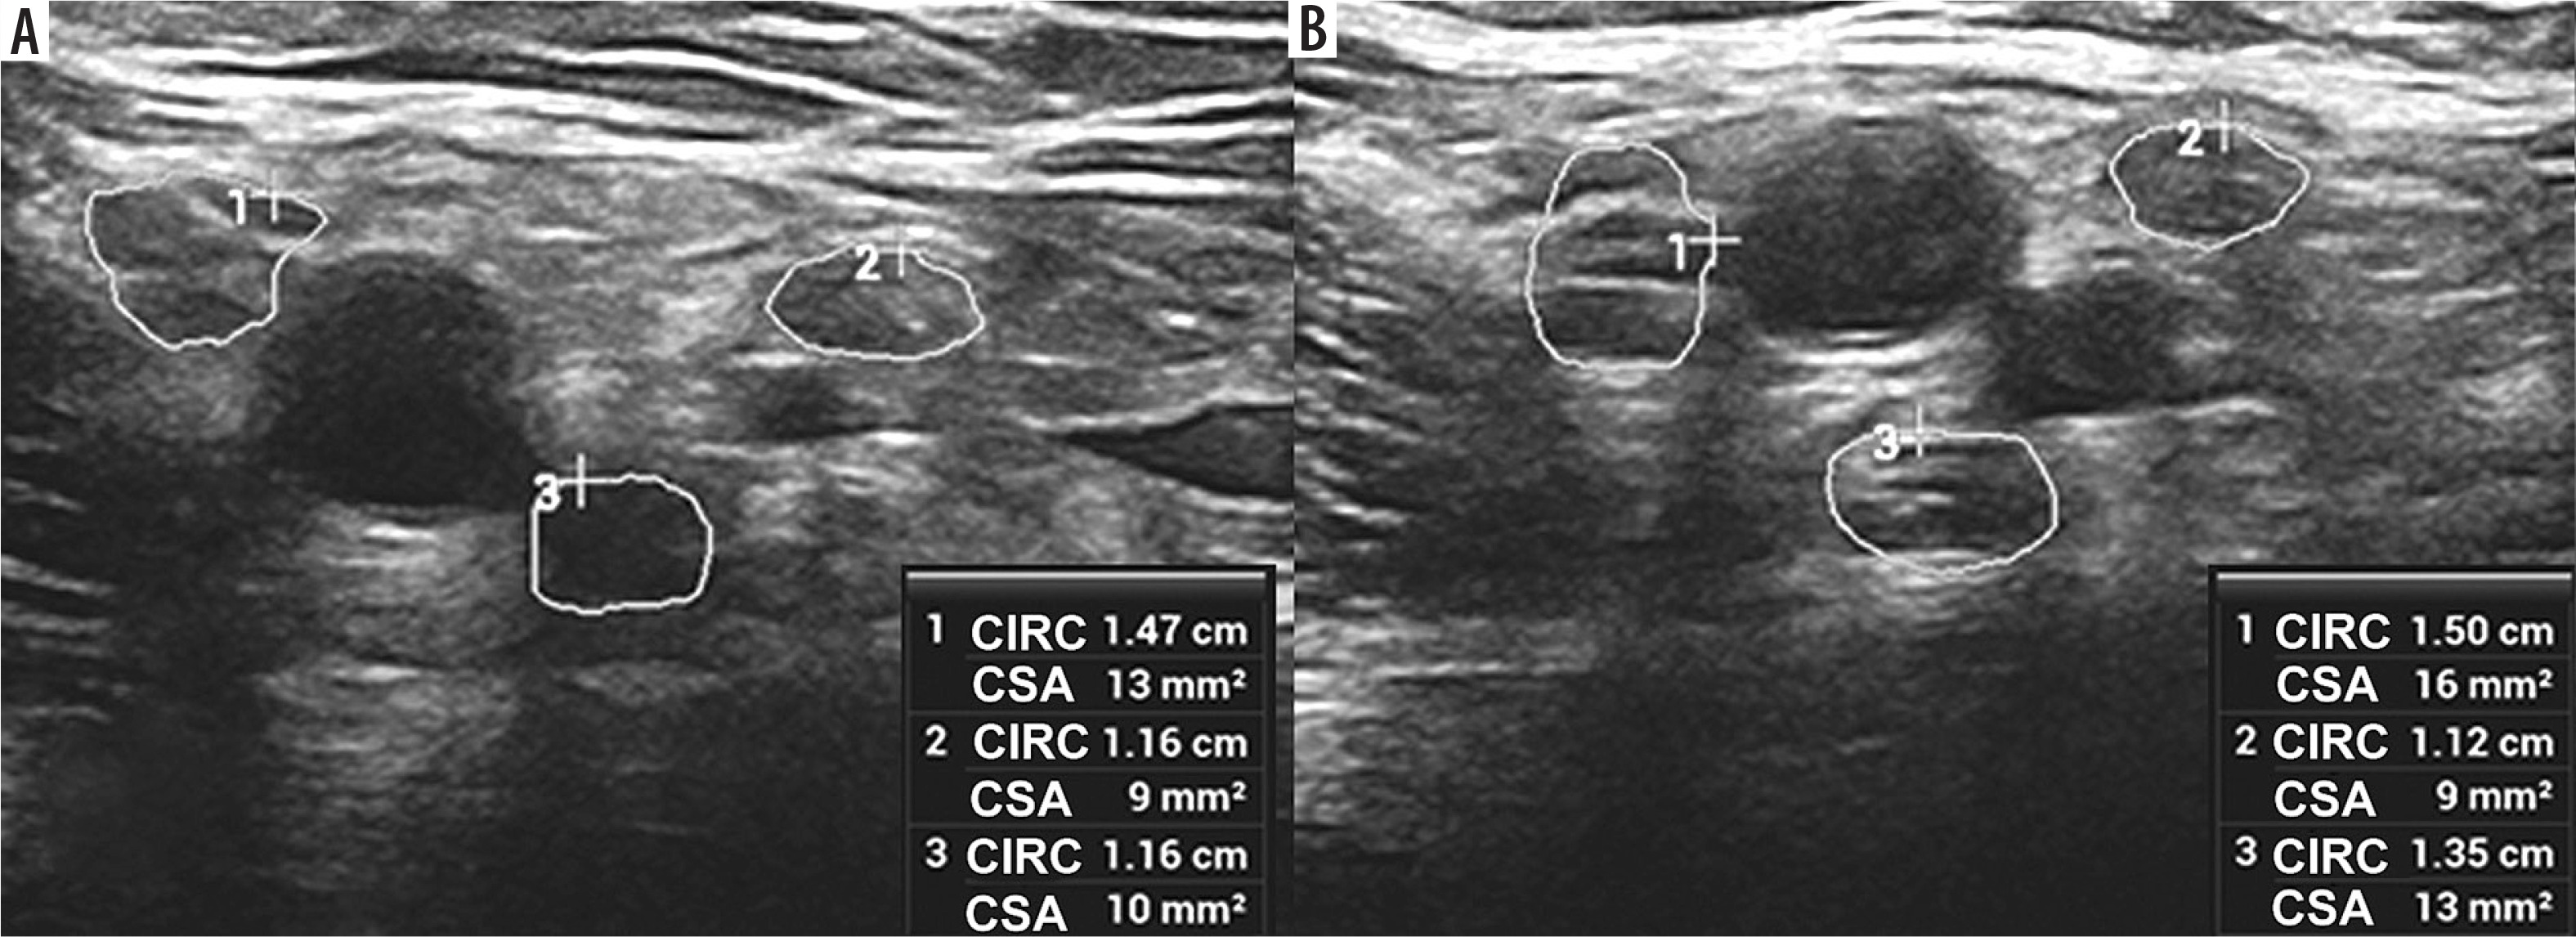

Figure 8

High-resolution ultrasound (HRUS) image of the brachial plexus in the region of the axilla with increased measurements of the lateral (1), medial (2) and posterior (3) cords of the symptomatic side in brachial neuritis due to neuroborreliosis with Banwarth syndrome. Images obtained by author with a 5-20 MHz linear probe of the Mindray Resona I9